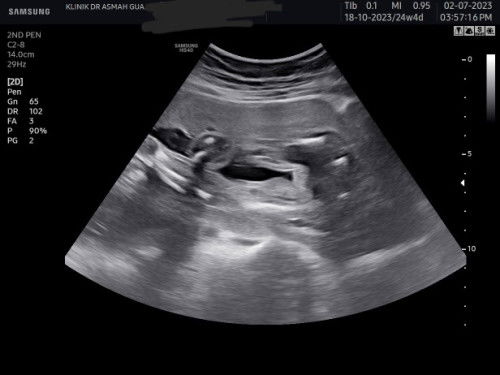

Scan baby boy or girl?

Salam ibu-ibu,..nak pinjam mata ibu-ibu kejap tolong tengok baby boy or girl. Dr xleh confirm boy or girl sbb burger and pistol xnampak. Saje-saje ni post..hehe Ape pon jantina semoga baby sihat walafiat. Amin #scan25weeks #detailscan #fistbaby